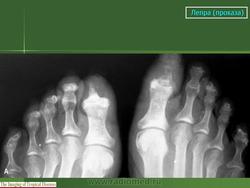

В третьей группе костных изменений при проказе (рис. 217, 218) сочетаются элементы первых двух групп, т. е. специфические и неспецифические. Из особенностей проказы вытекает крайняя неповторяемость частных проявлений в каждом индивидуальном случае заболевания.

Рентгенологическое исследование костно-суставной системы в некоторых случаях проказы выявляет довольно богатую картину изменений, когда с клинической стороны заболевание еще ничем себя не проявило или же внешних дерматологических, неврологических и т. п. данных еще мало для ответственного распознавания; положительная рентгенологическая симптоматика может и должна направить мысль лечащего врача в сторону устанавливающего диагноза проказы. Это особенно важно в отдельных спорадических случаях.

В нашем распоряжении имеется несколько наблюдений, когда путем рентгенологического исследования была Б раннем периоде диагностирована проказа.